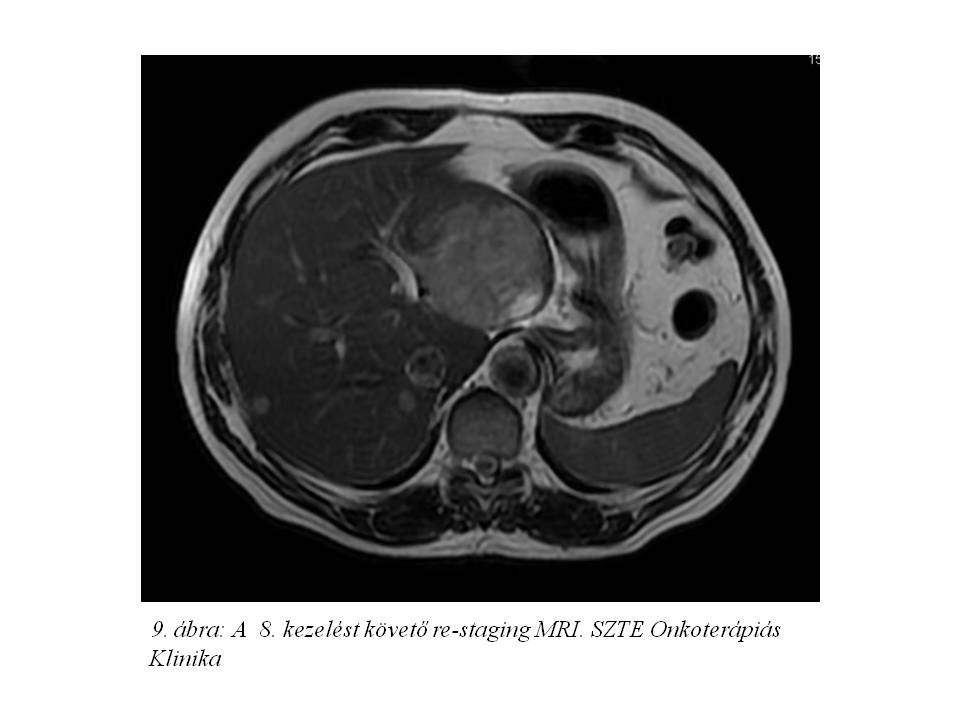

Octreotid monoterápiáját (Sandostatin LAR kezelés) 2012.04.27-én kezdtük, az első injekció beadását követően arcpirosodása és hasmenése megszűnt. A 4. kezelést követően re-staging MR vizsgálaton (8. ábra) minimális regressziót véleményeztek (2012.08.10.), chromogranin 128 ng/ml-re csökkent. A 8. kezelést követően képalkotóval továbbra is stabil betegség állt fenn, azonban a chromogranin érték emelkedni kezdett (185,4 – 197,30 – 200,5 – 266,0 – 283,9 ng/ml). A definitív progresszió hiánya (7%-os növekedés, SD) miatt kezelését folytattuk, összesen 22 ciklust kapott 2013.12.02-ig (9. ábra, 10. ábra).